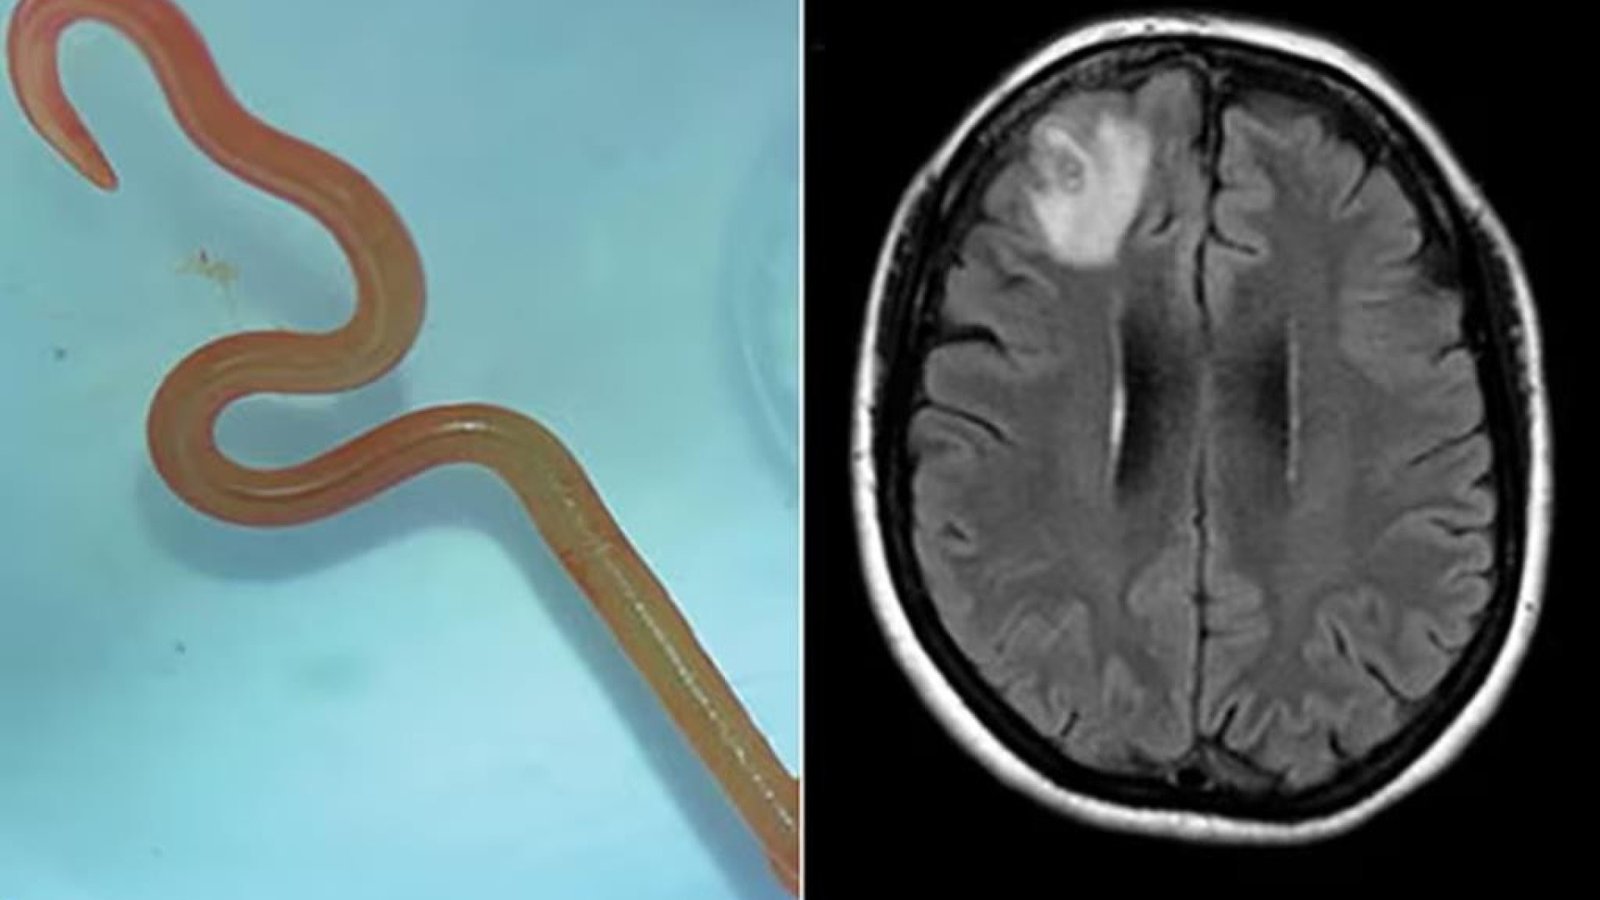

Verme com 8 cm é encontrado em cérebro

O neurocirurgião, Dr. Hari Priya Bandi, retirou um verme parasita de 8 centímetros de comprimento do cérebro de uma paciente, o que a levou a procurar Senanayake e outros colegas do hospital para obter conselhos sobre o que fazer a seguir.

Segundo o jornal The Guardian, a paciente já tinha sido internada em janeiro de 2021 com queixas de febre, dores abdominais e diarreia incessantes, tosse seca e suores noturnos. Em 2022, a estes sintomas juntaram-se sinais de depressão e perda de memória, o que levou ao seu encaminhamento para o hospital de Canberra. Feita uma ressonância magnética que revelava algumas anomalias, a mulher foi operada ao cérebro.